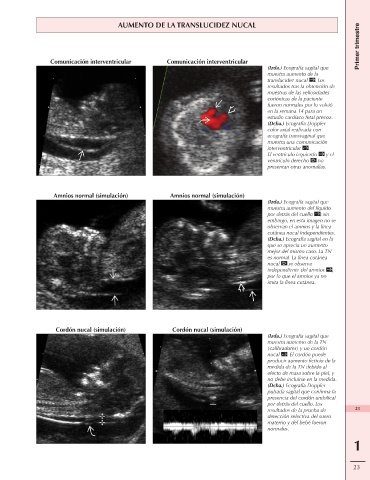

AUMENTO DE LA TRANSLUCIDEZ NUCAL

Comunicación interventricular Comunicación interventricular

(Izda.) Ecografía sagital que

muestra aumento de la

translucidez nucal . Los

resultados tras la obtención de

muestras de las vellosidades

coriónicas de la paciente

fueron normales por lo volvió

en la semana 14 para un

estudio cardíaco fetal precoz.

(Dcha.) Ecografía Doppler

color axial realizada con

ecografía transvaginal que

muestra una comunicación

interventricular .

El ventrículo izquierdo y el

ventrículo derecho no

presentan otras anomalías.

Amnios normal (simulación) Amnios normal (simulación)

(Izda.) Ecografía sagital que

muestra aumento del líquido

por detrás del cuello ; sin

embargo, en esta imagen no se

observan el amnios y la línea

cutánea nucal independientes.

(Dcha.) Ecografía sagital en la

que se aprecia un aumento

mejor del mismo caso. La TN

es normal. La línea cutánea

nucal se observa

independiente del amnios ,

por lo que el amnios ya no

imita la línea cutánea.

Cordón nucal (simulación) Cordón nucal (simulación)

(Izda.) Ecografía sagital que

muestra aumento de la TN

(calibradores) y un cordón

nucal . El cordón puede

producir aumento ficticio de la

medida de la TN debido al

efecto de masa sobre la piel, y

no debe incluirse en la medida.

(Dcha.) Ecografía Doppler

pulsada sagital que confirma la

presencia del cordón umbilical

por detrás del cuello. Los

resultados de la prueba de 23

detección selectiva del suero

materno y del bebé fueron

normales.